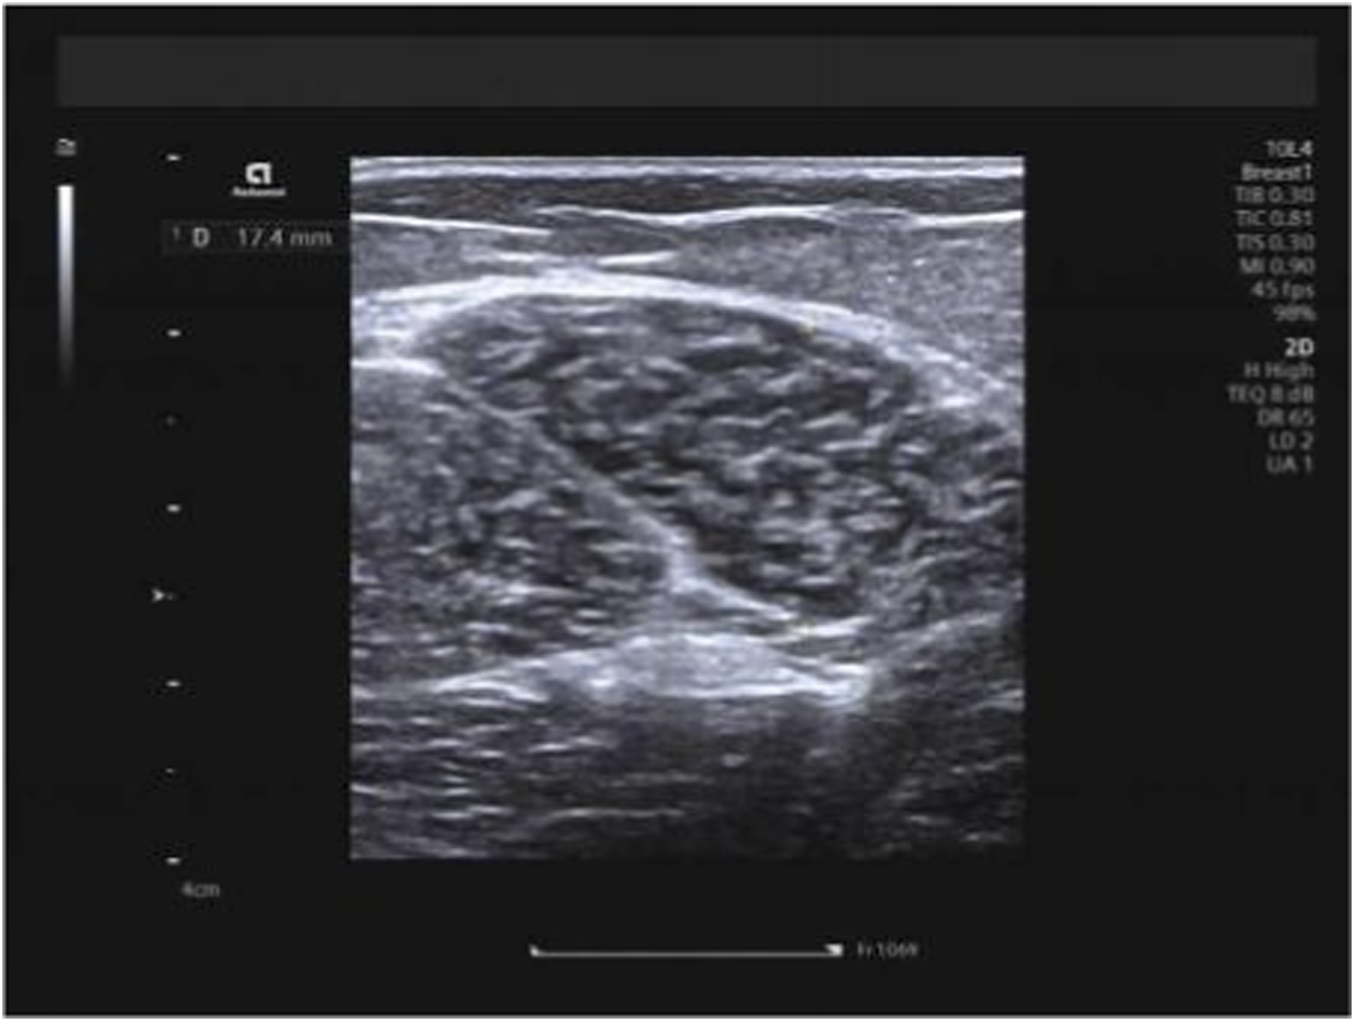

Hamstring muscles (specifically the long head of the biceps femoris and semitendinosus) were examined with participants in the prone position, legs extended naturally and body fully relaxed. The measurement site was standardized as the mid-belly region of each muscle, located approximately 15 cm distal to the ischial tuberosity along the longitudinal axis of the muscle fibers. Muscle thickness was measured on B-mode ultrasound images as the vertical distance between the superficial and deep fascia at this site, with the transducer placed transversely to the muscle fibers. Three consecutive measurements were taken and averaged to obtain the final value (Figures 2, 3). Hamstring measurements were obtained in two positions: the neutral position and the 90° knee-flexed position. During measurements performed at 90° knee flexion, the angle was maintained using a custom foam pad positioned beneath the lower leg to support the shank, ensuring a consistent 90° angle between the femur and tibia. The participant’s position was monitored throughout image acquisition to prevent unintended movement or muscle activation. In this study, measurement posture refers to the specific body position adopted during imaging (e.g., neutral, flexed, or extended), and measurement technique refers to the probe orientation or imaging plane (transverse or longitudinal) used during shear-wave elastography. Importantly, for all examined muscles—including the upper trapezius, biceps femoris long head, and semitendinosus—SWE measurements were performed in both longitudinal and transverse planes at the same anatomical locations. To ensure methodological consistency, the acquisition depth was standardized for each muscle group: 0.5–1.0 cm for the upper trapezius and 1.0–2.0 cm for the hamstring muscles (long head of the biceps femoris and semitendinosus), with minor adjustments made only to ensure that the ROI was positioned at the center of the muscle belly. A fixed 1.0 × 1.0 cm circular region of interest (ROI) was applied uniformly across all measurements. This dual-orientation approach was intentionally implemented to evaluate the consistency and direction-dependent characteristics of muscle stiffness, in accordance with previous recommendations.

FIGURE 2

Measurement of biceps femoris long head thickness.